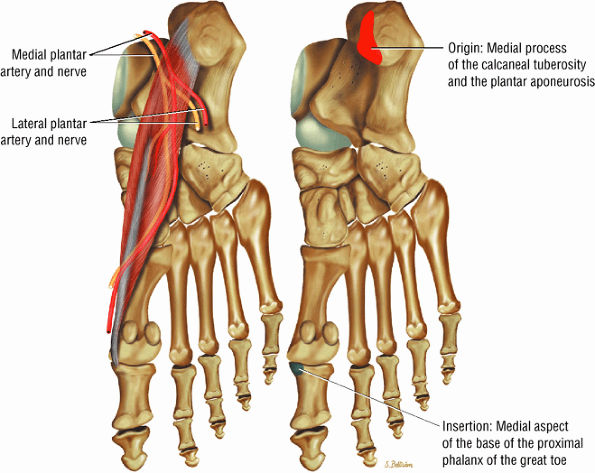

The muscles of the foot are the extensor digitorum brevis (Fig. 5.14), the abductor hallucis (Fig. 5.15), the flexor digitorum brevis (Fig. 5.16), the abductor digiti minimi (Fig. 5.17), the quadratus plantae (Fig. 5.18), the lumbricals (Fig. 5.19), the flexor hallucis brevis (Fig. 5.20), the adductor hallucis (Fig. 5.21), the flexor digiti minimi brevis (Fig. 5.22), the dorsal interossei (Fig. 5.23), and the plantar interossei muscles (Fig. 5.24).

FIGURE 5.15 ● ABDUCTOR HALLUCIS The abductor hallucis functions in abduction of the great toe. In tarsal tunnel syndrome the medial and lateral plantar nerves may be decompressed by releasing the fascia of the abductor hallucis muscle.